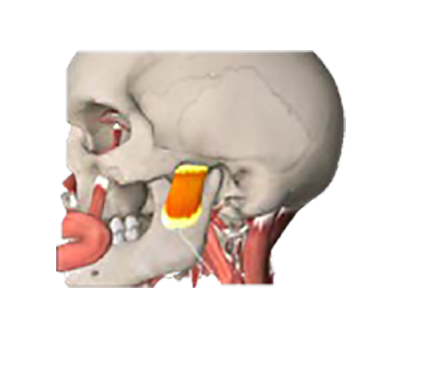

De spieren die bij stress vooral samentrekken zijn:

1. Wangkauwspier

2. Borstbeen-sleutelbeen-tepelspier

1

2